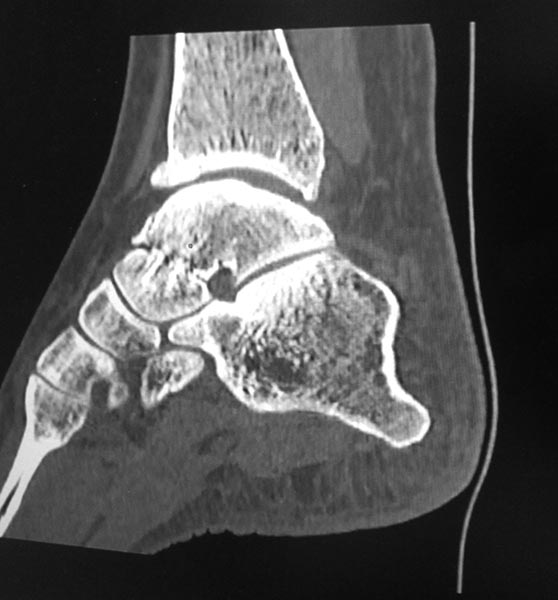

Я бы еще повниматьнее к таранной кости присмотрелся. Не было ли перелома ее шейки? На КТ срез подозрительный, но только один.

Я тоже согласен, на одном из КТ-снимков, подозрение на перелом шейки таранной кости.

Также есть подозрение на перелом таранной кости по КТ.

Желательно все-таки точно убедиться в наличии перелома таранной кости. Если он не сросся за 3 года, то ситуация становится еще более непонятной. Ждем снимков под нагрузкой и дополнительных срезов КТ.

Вколоченный перелом шейки таранной шейки кости,переднего края Б/берцовой кости.МОС шейки таранной кости,удаление костно-хрящевых экзостозов.